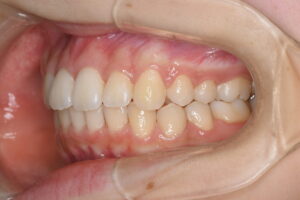

▼治療後の口腔内写真1

▼治療後の口腔内写真2